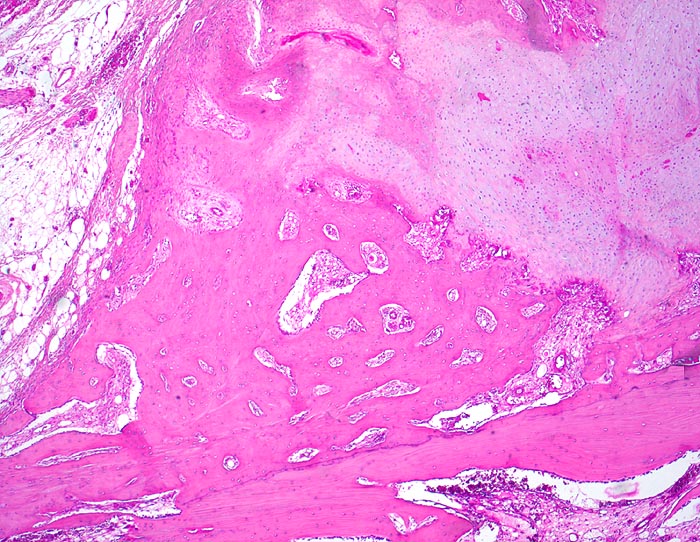

sekundäre Frakturheilung: Kallus

Dem Frakturspalt aussen aufsitzender knöcherner und knorpliger Kallus mit Zonen der enchondralen Ossifikation. Extraperiostales Fettbindegewebe.

Konservativ behandelte Rippenfraktur nach Sturz vor einem Monat.

Die Frakturenden werden durch den Kallus überbrückt. In der Frühphase der Heilung wird ein Übermass an Bindegewebe, Knorpel und Knochen gebildet vor allem bei ungenügender Ruhigstellung. Während der Ausreifung des Kallus werden diejenigen Gewebsanteile, welche keiner erhöhten Belastung ausgesetz sind, wieder resorbiert. Der Kallus wird im Verlauf der Zeit zunehmend kleiner.